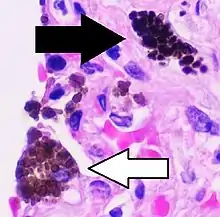

Cytology of a macrophage with typical features. Wright stain.

Pigmented macrophages can be classified by the pigment type, such as for alveolar macrophages shown above (white arrows). A "siderophage" contains hemosiderin (also shown by black arrow in left image), while anthracotic macrophages result from coal dust inhalation (and also long-term air pollution).[52] H&E stain.